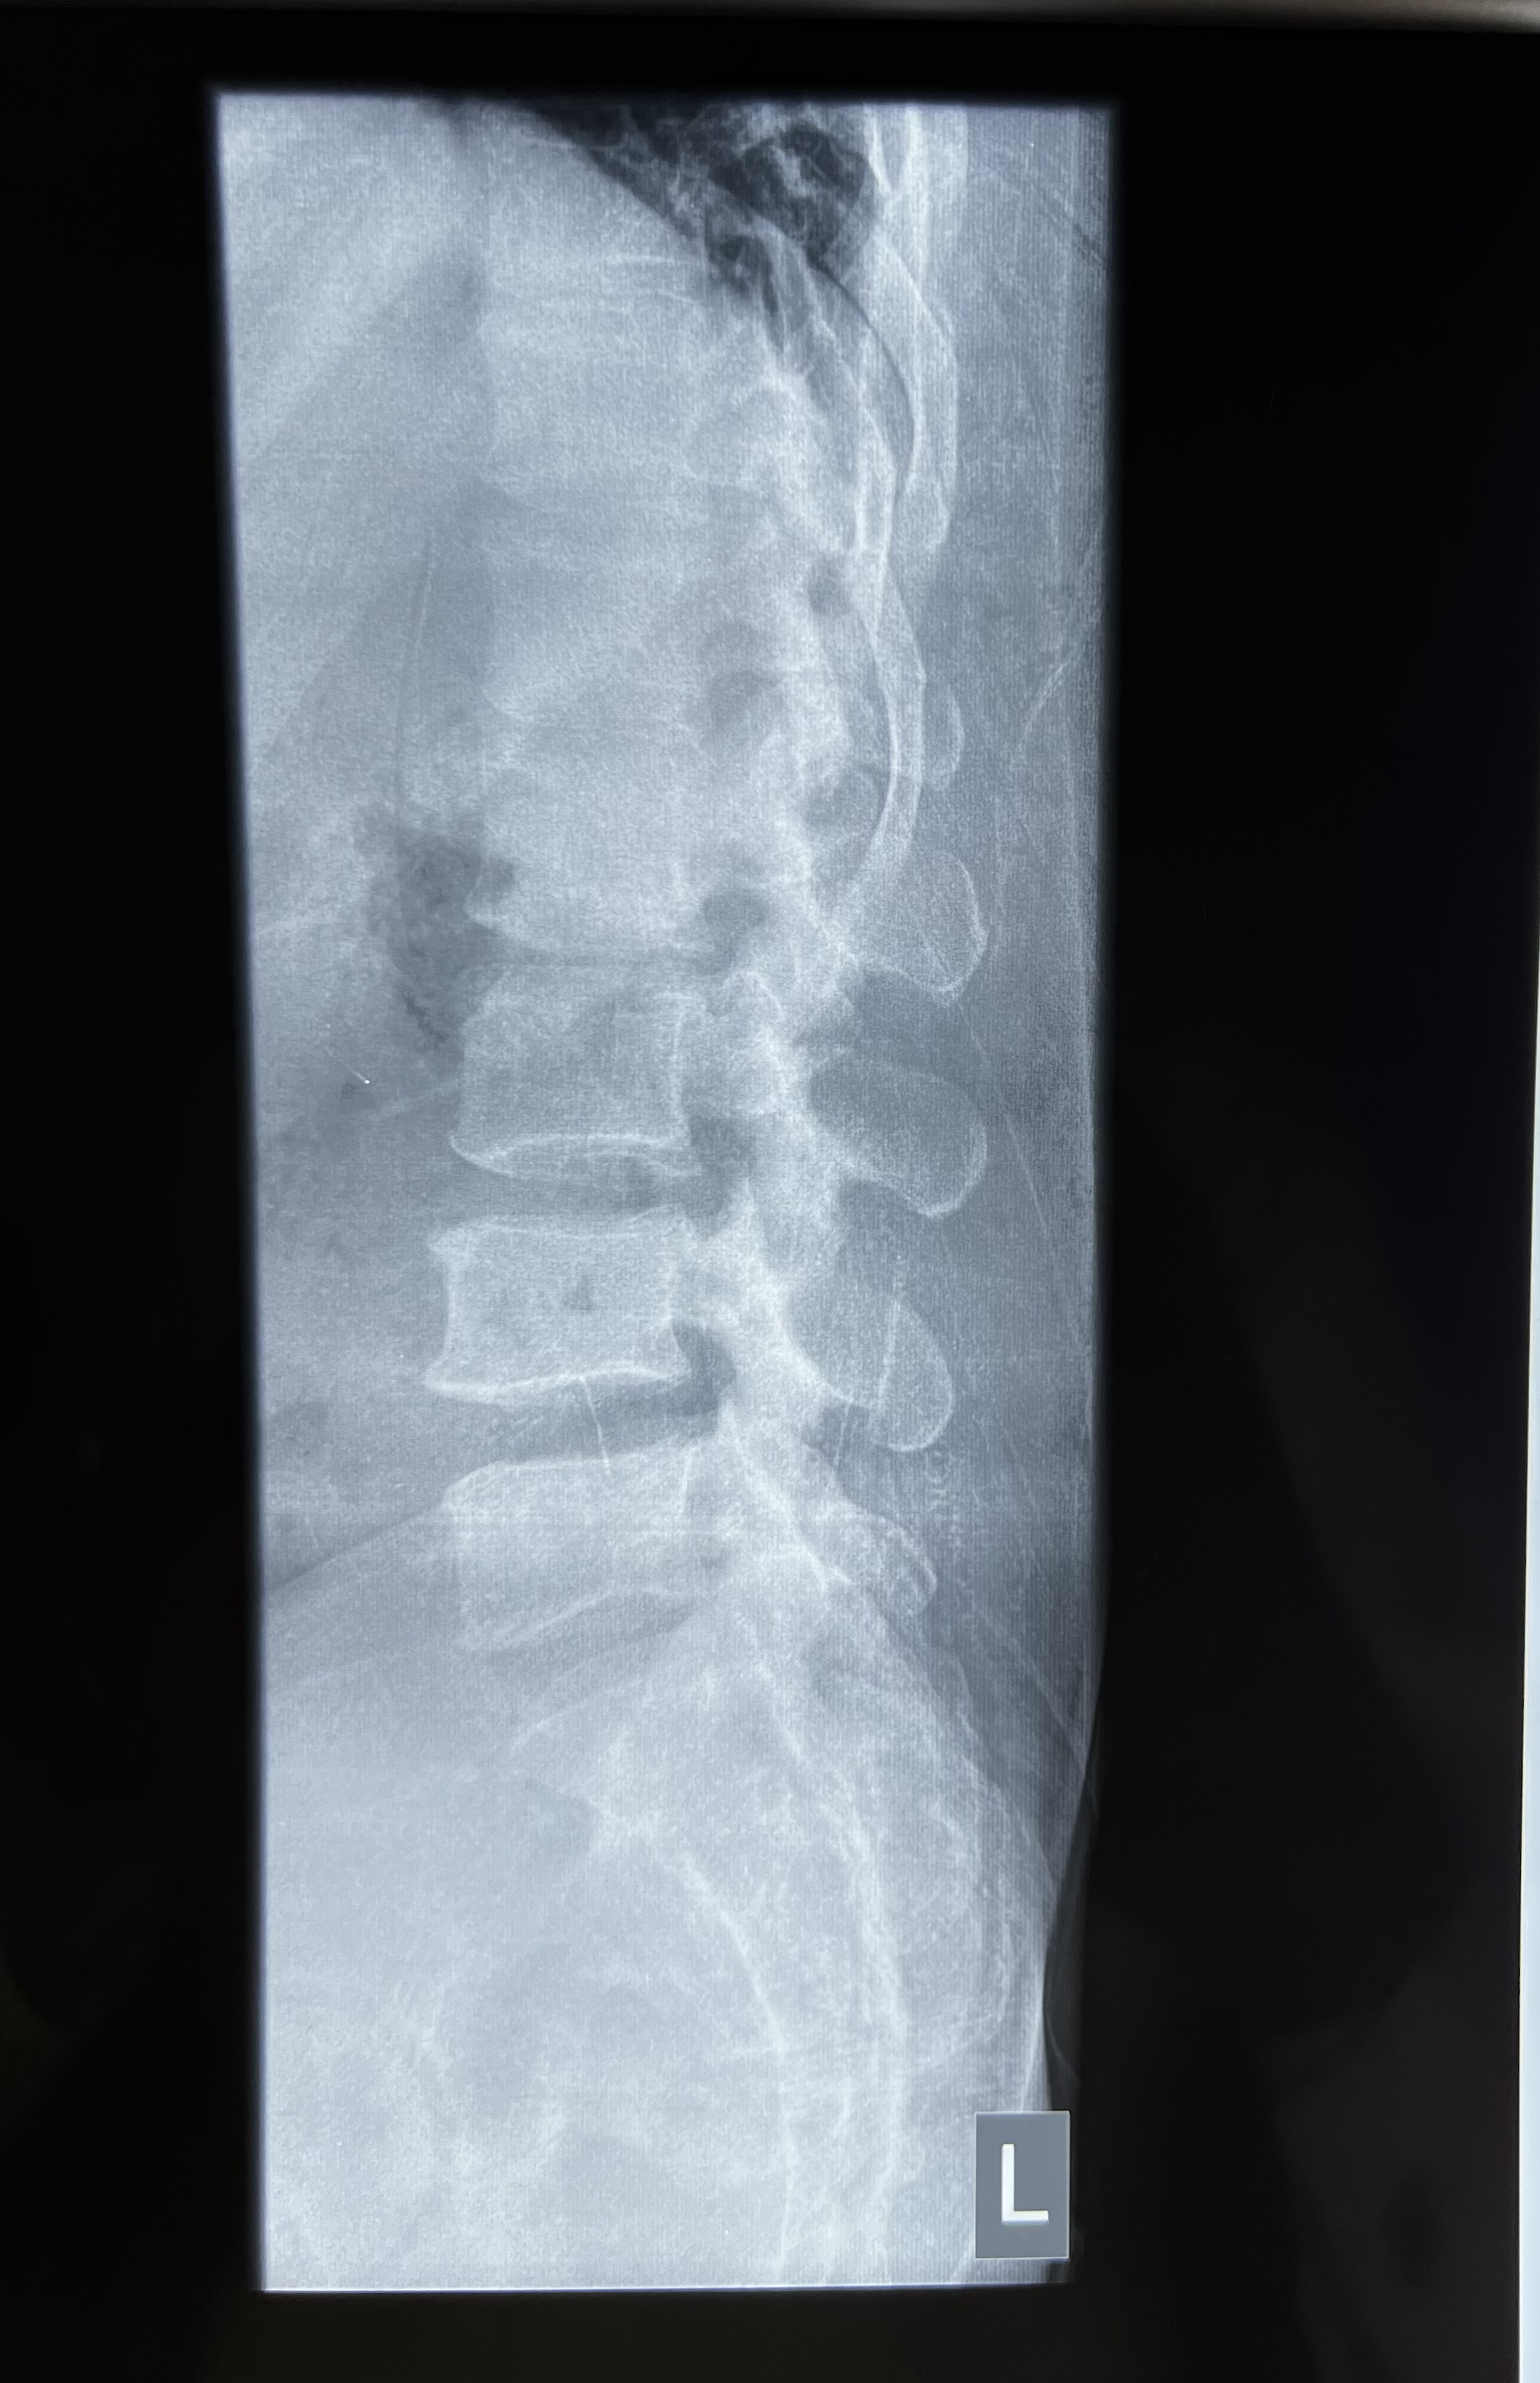

Radiology